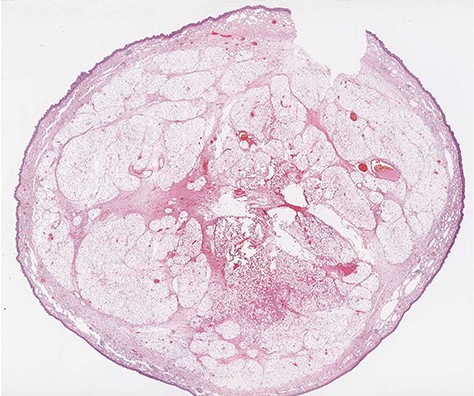

Microscopic transverse section revealing a benign tumor composed of a large amount of mature adipocytes with a flat peripheral nucleus without atypia, surrounded by fibrous tissue and containing rare blood vessels (H&E stain, ×10).